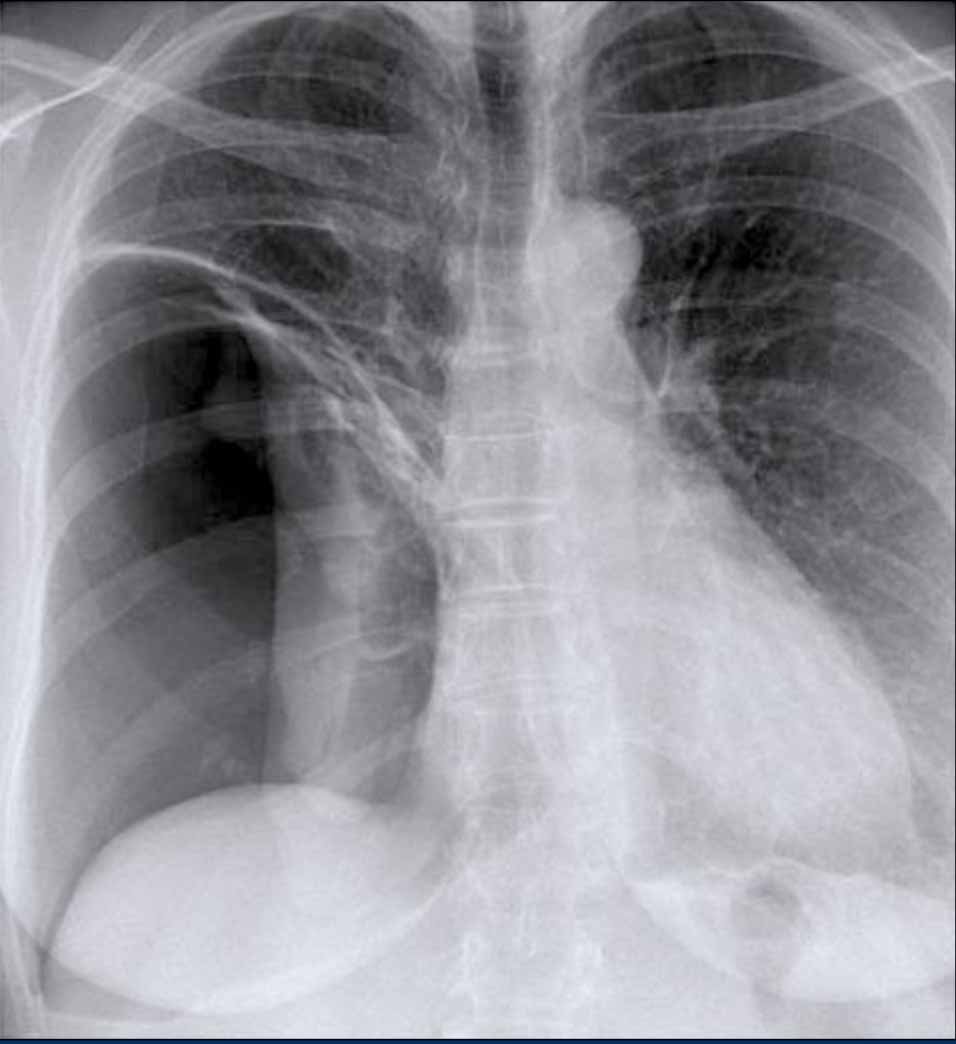

Case Example: Subtle Signs of Congestive Heart Failure

Begin by reviewing these current chest radiographs.

Based solely on these images, one might suspect congestive heart failure (CHF), though the findings are subtle.

Now review the previous study…

Scrolling between the current and prior films significantly increases diagnostic confidence in your diagnosis of congestive heart failure.

Key comparative findings include:

- Cardiac size: Slightly increased compared to the previous study; however, cardiomegaly was already present.

- Pulmonary vasculature: Mild vascular engorgement suggesting elevated pulmonary venous pressure.

- Interstitial markings: Subtle signs of interstitial edema .

- Pleural effusions: Bilateral small effusions, with subtle changes in the inferoposterior borders of the lower lobes, suggesting fluid accumulation.